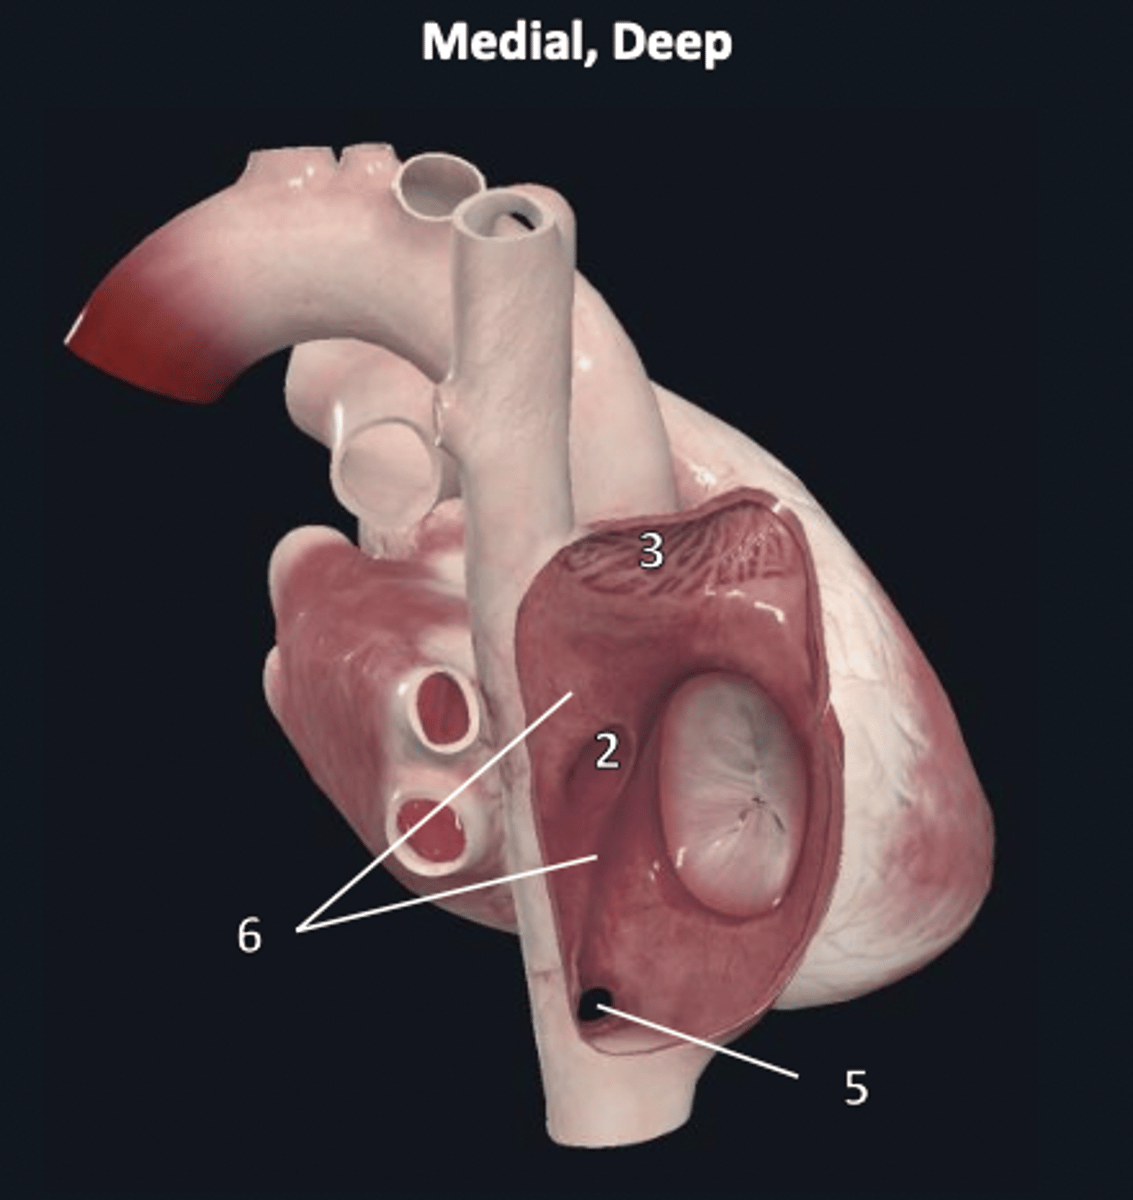

right ventricle

1

trabeculae carneae

2

septal papillary muscle

3

anterior papillary muscle

4

inferior papillary muscle

5

chordae tendineae

6

moderator band

7

tricuspid valve

8

pulmonary semilunar valve

9

interventricular septum

10